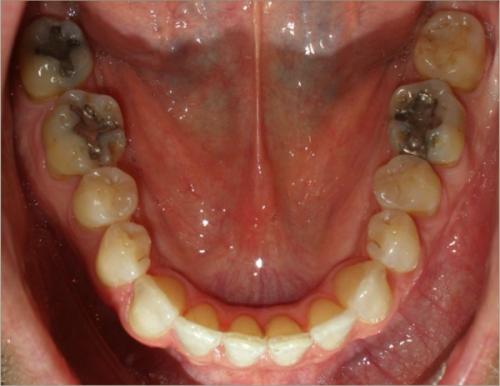

42 year old male:

Diagnosis:

- Skeletal underbite

- Retruded upper jaw, protruded lower jaw

- Full arch crossbite

- Lower arch crowding

Treatment:

- Non-Extraction

- Full fixed appliances

- Double jaw surgery

- 20 months